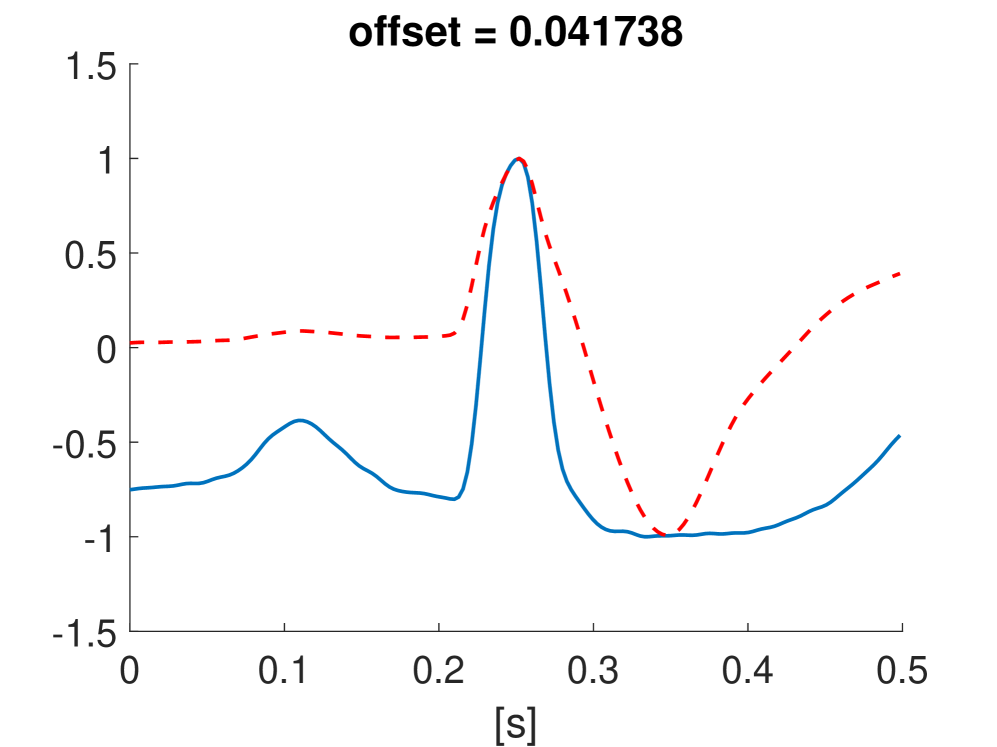

Fig. 10 shows the result in input space of moving along the first principal components in the latent feature space. As original base point we take a normal beat signal, i.e. corresponding to a hidden unit on the bottom right of Fig. 9(a). The smooth transition between the beat patterns allows for interpretation of the first principal components. This allows a clinical expert to understand on what basis the paced beats are separated by the principal components and if this basis has a physiological meaning. In order to investigate the separated region of the latent space at the top of Fig. 9(b) we start from a paced beat pattern and vary along the third principal component. This allows us to see which sort of heartbeat patterns are responsible for this specific distribution in the latent space.